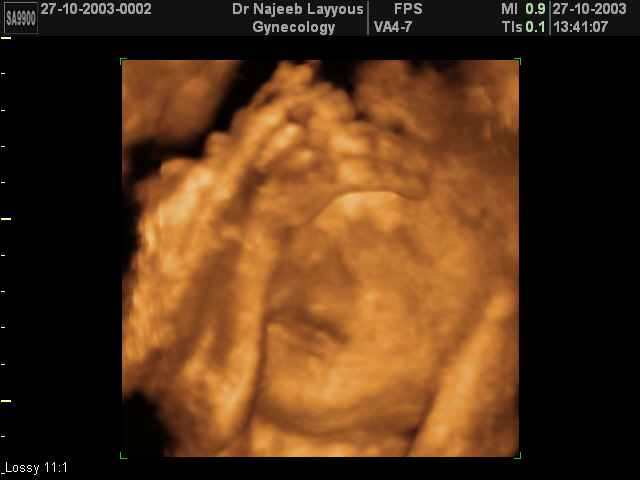

- Fetal Behavior Ultrasound Photos

Ultrasound Photos in 3D showing Fetal Behavior Inside the uterus | Dr N Layyous